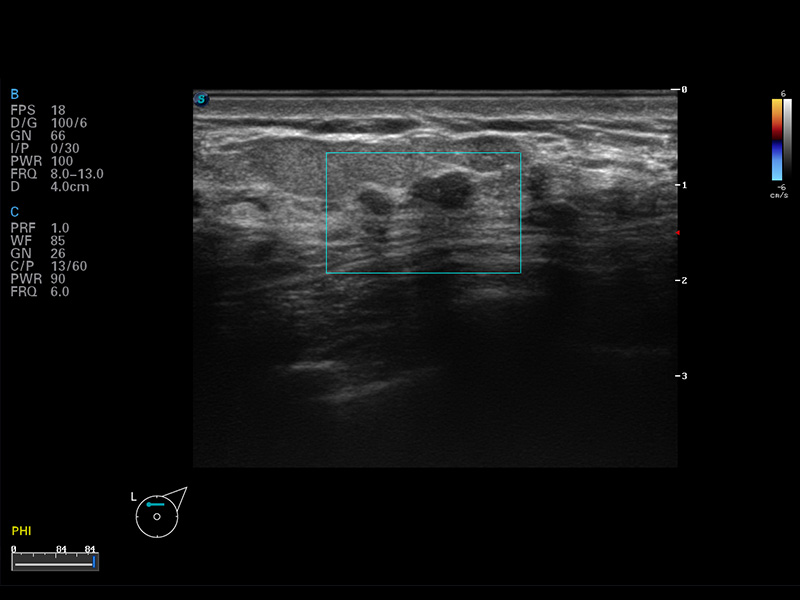

μ-Scan微米成像

谐波成像

空间复合成像